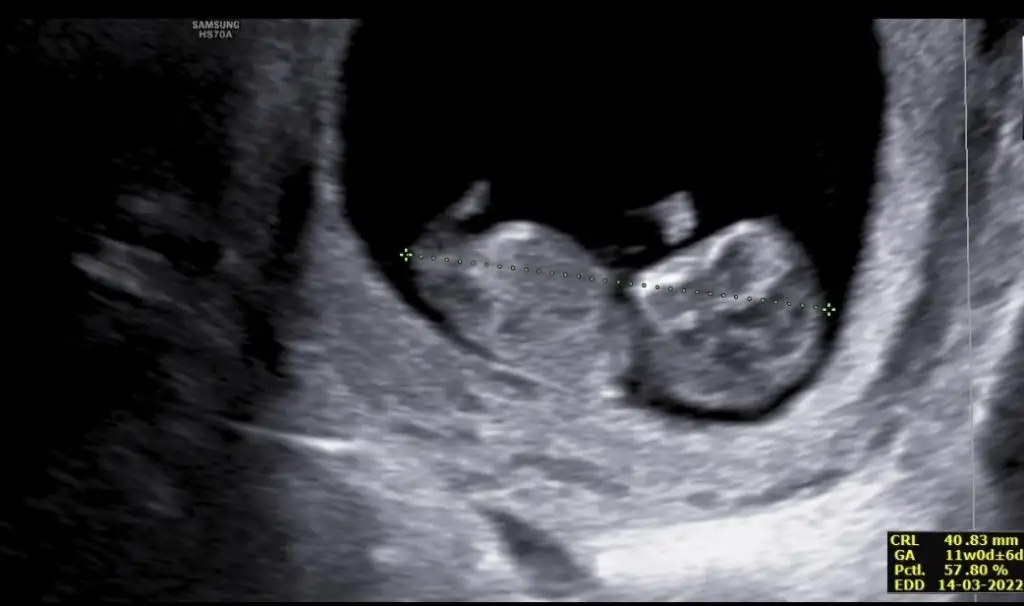

Merhaba bana da tahmin yapabilir misiniz?Erkek ve kız için 11 + 12+ yada 13 hafta usg görüntüsü olmalı açıklamalar asagıda yazıyorrabbim herkesin gönlüne göre nasip etsin inşallah .. ecmain

[/B]Eki Görüntüle 473828 gordugunuz gibi ust taraftaki simgedende anlasildigi gibi eger cikinti paralel ise kiz

yok 30°lik bir aciyla yukari dogru bakiyorsa %99 oglunuz olacak demektir simdi bi kac ornek resimler daha koyacagim kiziminkide dahil

Eki Görüntüle 473829 bu bir erkek bebek genital nub cikintisi gayet yukarda

Eki Görüntüle 473831 simdi burada cikintilara bakin eger bel popo cizgisine paralel ise kiz

yok 30 derecelik bir aciyla yukari bakiyorsa erkek

yabancilarin hepsi biliyor bunu biz neden eksik kalalim gayet bilimsel simdi ellerinde11 12 13 ultrason fotografi olanlar alsin hemen baksin yada koyalim buraya